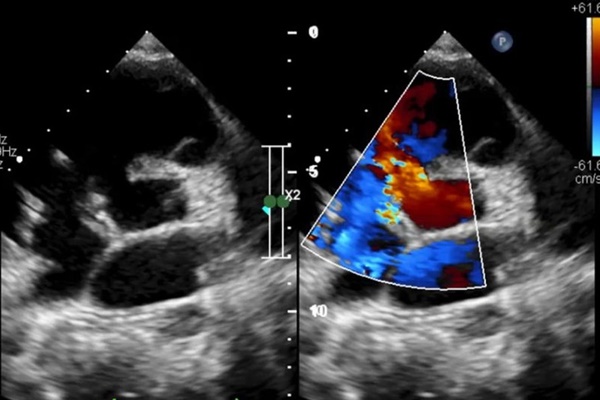

Ca phẫu thuật tách dính cặp song sinh (ảnh tư liệu).